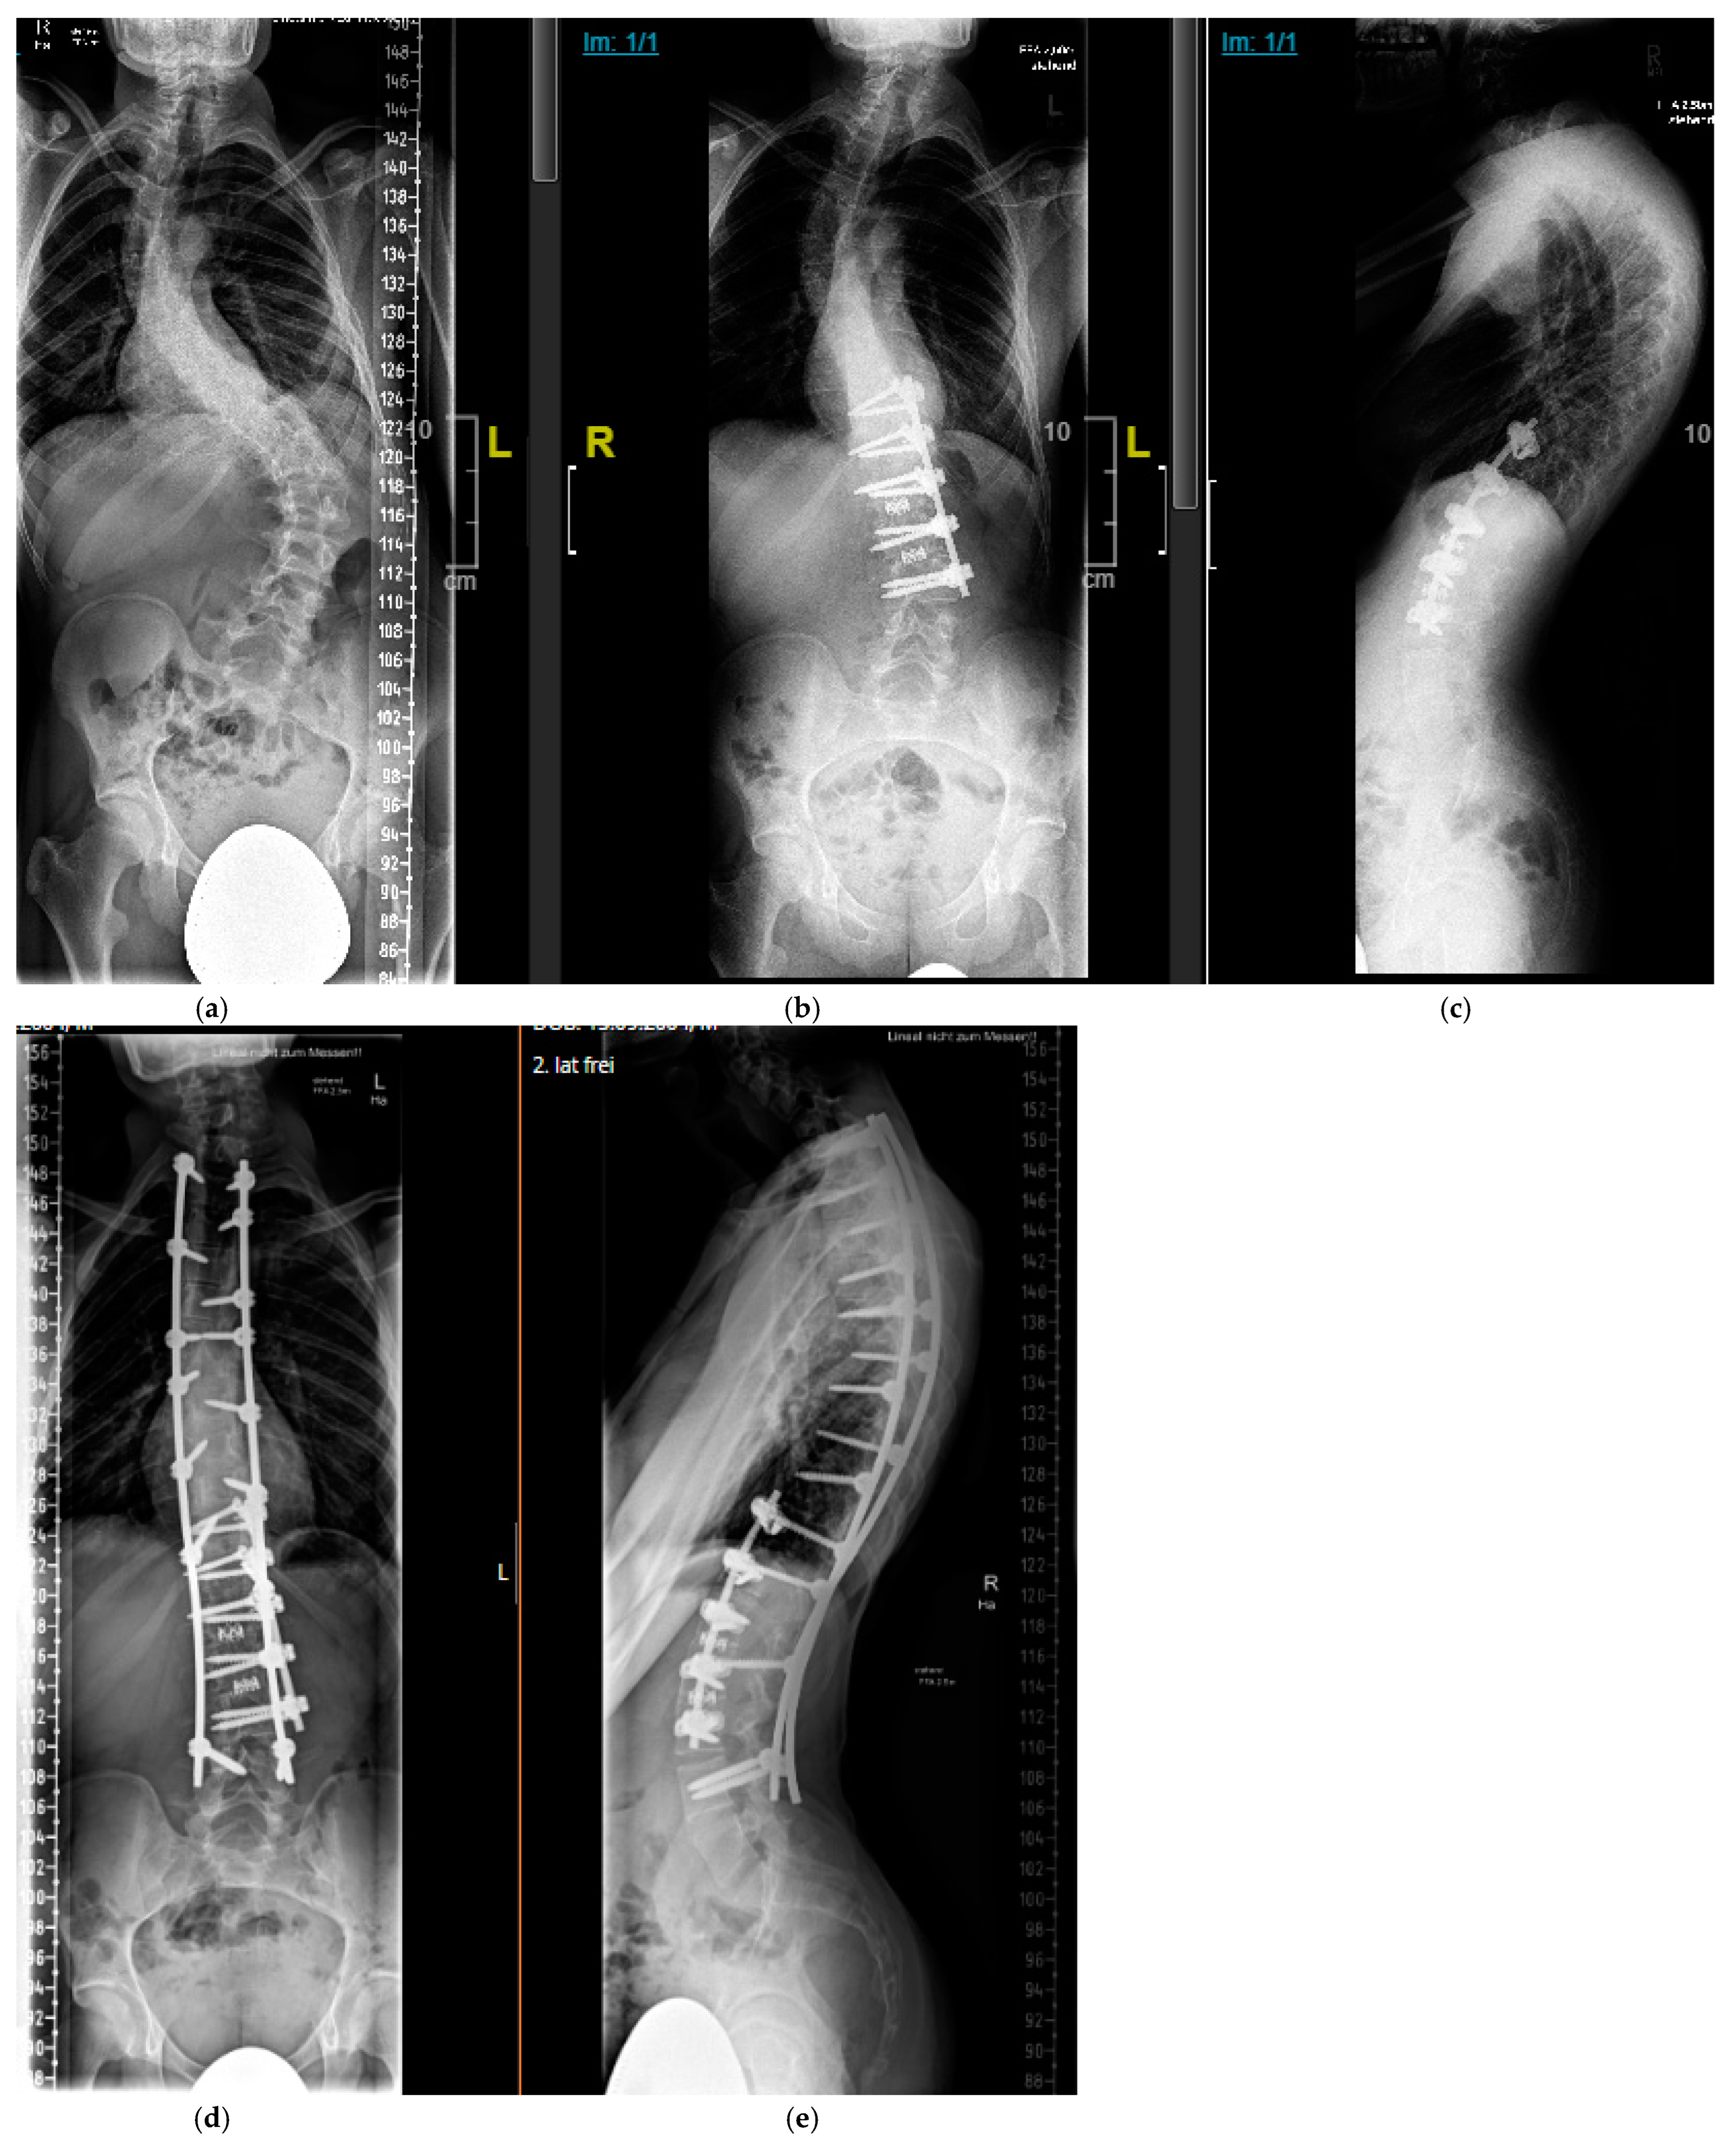

4.2.1. “Early Onset Spinal Deformity”

4.2.2. Adolescent Spinal Deformity

5.2.1. Growth-Preserving Techniques

5.2.2. Definitive Spinal Fusion